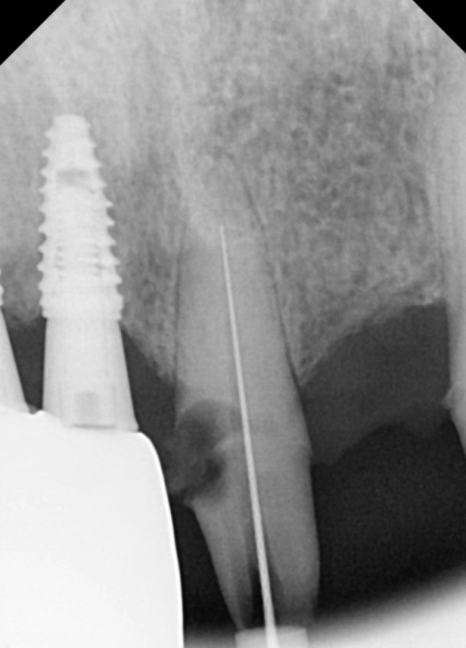

먼저 충치가 심했던 앞니(#21)부터

치료를 시작했습니다.

충치를 깨끗하게 걷어내고,

감염된 신경을 제거하는

신경치료를 꼼꼼하게 진행했죠.

#21 신경치료 과정

워낙 충치가 깊어서 걱정했지만,

다행히 신경치료가 잘 마무리되어

치아를 살려 쓸 수 있게 되었습니다.

그리고 바로 이어서 수술을 진행했는데요.

브릿지 연결 부위였던 치아 없는 자리는

다행히 잇몸 뼈가 아주 튼튼했습니다.

230614

덕분에 환자분이 힘들어하시는

뼈이식 과정 없이,

아주 수월하게 임플란트를 식립할 수 있었죠.